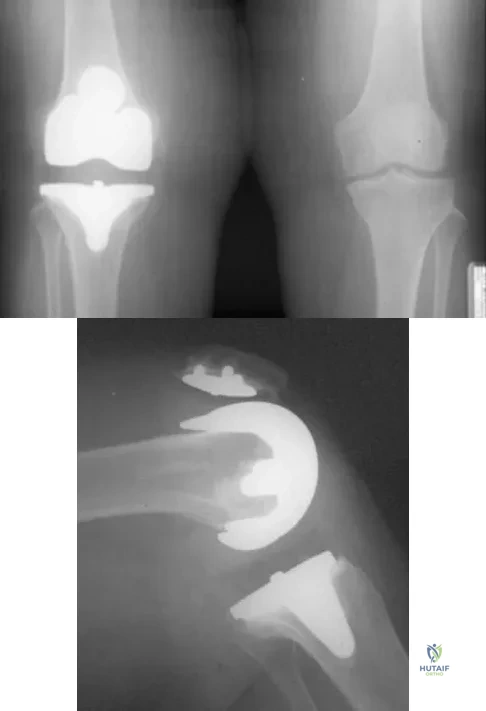

Figures 57a through 57c show the radiographs of a patient who has pain, discomfort, and a popping sensation localized to the posterior aspect of the knee after undergoing primary left total knee arthroplasty 6 months ago. Examination reveals that the patient is able to ambulate without a limp. There is no significant swelling, erythema, or effusion. Range of motion is 0 degrees to 115 degrees, and a palpable crepitation or snapping is detected at the posterior lateral joint line. What is the most likely diagnosis?

A 63-year-old woman reports giving way of the knee and pain after undergoing primary total knee arthroplasty (TKA) 1 year ago. Examination reveals that the knee is stable in full extension but has gross anteroposterior instability at 90 degrees of flexion. The patient can fully extend her knee with normal quadriceps strength. Studies for infection are negative. AP and lateral radiographs are shown in Figures 12a and 12b, respectively. What is the appropriate management?